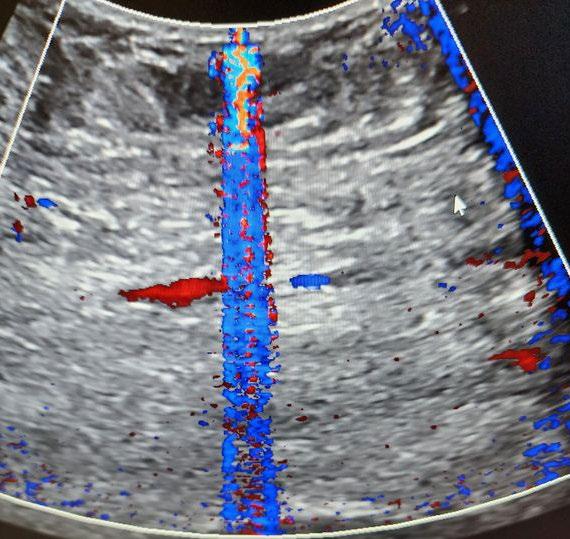

WHAT DO COLOR DOPPLER ARTIFACTS LOOK LIKE?

Well, the term artifact refers to any unwanted and unexpected anomaly in an image. Typically, color artifacts appear as unwanted flashes, vertical streaks, or areas of non-descript color variations in the image. Take a look at the photos.

WHAT ARE SOME CAUSES OF COLOR ARTIFACTS?

There are many root causes, and some lie within the scanner console itself. For this discussion, let’s assume that the scanner is working as expected. One of the most common root causes is worn and intermittent wires in the probe’s wiring harness. As intermittent wires make, and break, contact with one another, the unwanted/unexpected electronic information will be displayed as flashing lines or color streaks in color

Doppler mode. In pulse wave and continuous wave Doppler modes, the same information is expressed as audio static. The exact location of the flashing lines in the image is directly related to one or more intermittent micro-coaxial wires in the wiring harness. One of our most common probe repairs is replacing a worn, intermittent wiring harness.